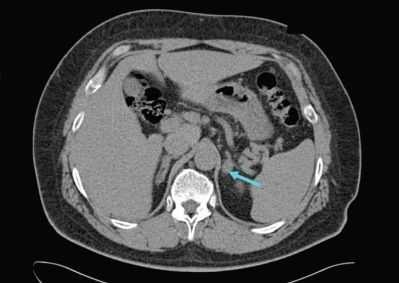

Для пациентов с доказанным первичным гиперальдостеронизмом следующим шагом является выяснение, каким заболеванием он вызван, — односторонним или двусторонним. Это очень важно, так как лечение каждого из них отличается. Компьютерная или магнитно-резонансная томография позволяют увидеть, есть ли опухоль в надпочечнике. Если пациент младше 40 лет и у него есть опухоль только в одном надпочечнике, то в этом случае можно приступать к лечению. Если пациент старше 40 лет и/или у него либо нет опухоли, либо есть опухоль, но в обоих надпочечниках, то возникает необходимость в проведении специального теста — селективного забора венозной крови из центральной вены надпочечников. В ходе этого теста хирург или рентгенолог берёт кровь непосредственно из вен обоих надпочечников, чтобы определить, какой именно орган вырабатывает патологическое количество гормона.

УЗИ надпочечников — низкочувствительный метод диагностики. Предпочтительнее проводить КТ: она помогает выявить как макро- и микроаденомы надпочечников, так и утолщения ножек надпочечников, гиперплазии и другие изменения [14] .

Для уточнения формы гиперальдостеронизма (одностороннего и двустороннего поражения) проводится селективный забор крови из вен надпочечников в специализированных центрах [9] . Это исследование эффективно снижает риск необоснованного удаления надпочечника только по данным КТ [4] .

- Инструментальная визуализация. УЗИ надпочечников и радиоизотопное сканирование (сцинтиграфию) надпочечников используют для выявления имеющихся патологических изменений и уточнения их характера (гиперплазия, опухоль), КТ надпочечников и МРТ надпочечников - для определения локализации и величины альдостеромы.